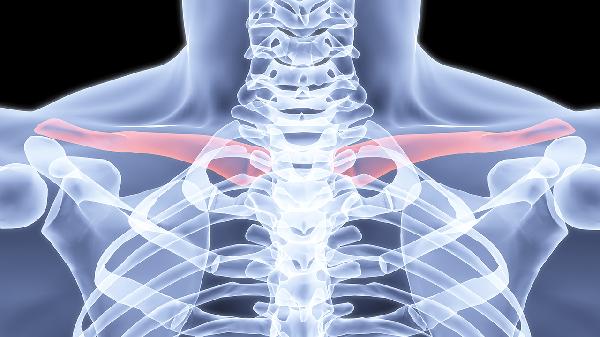

四肢骨折外固定后注意事项

四肢骨折外固定后,护理和康复是关键,直接影响恢复效果。外固定通常用于稳定骨折部位,帮助骨骼愈合,但固定期间需要注意很多细节,才能避免并发症并加快恢复。骨折后,外固定器或石膏会限制患肢的活动,目的是让骨骼在正确的位置愈合。固定期间,血液循环可能会受到影响,肌肉也可能因为缺乏活动而萎缩。如果不注意护理,可能会出现肿胀、疼痛、皮肤问题,甚至影响骨折愈合的速度。固定期间,保持患肢的清洁和干燥非常重要。石膏... ...